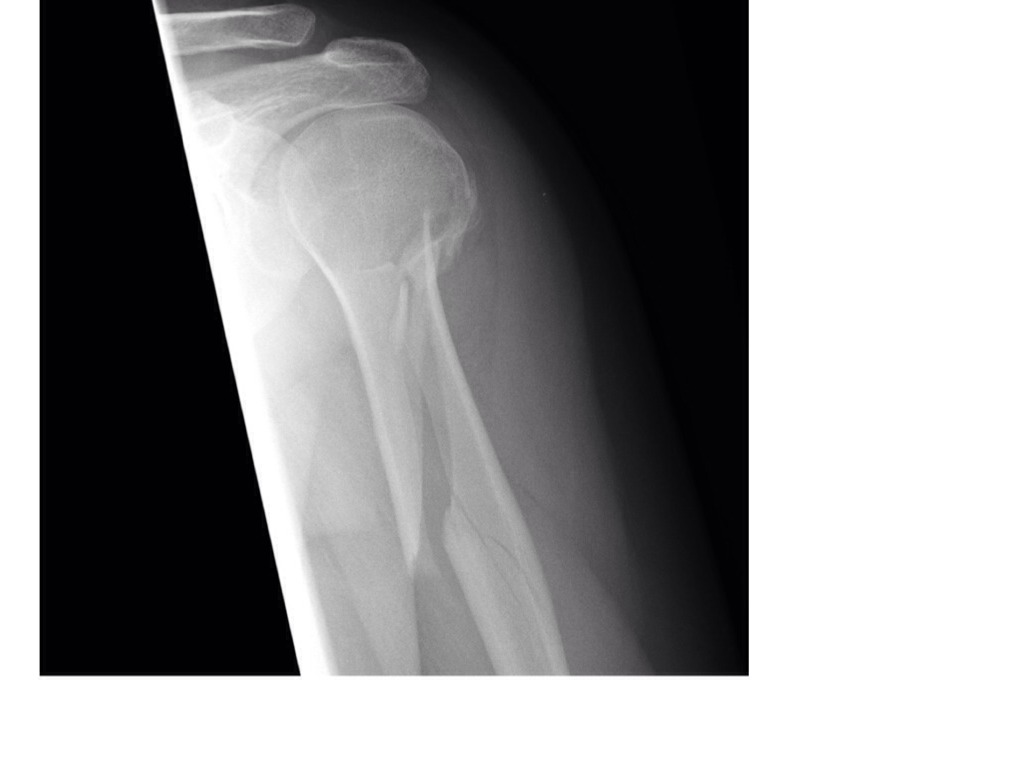

GROWTH PLATES